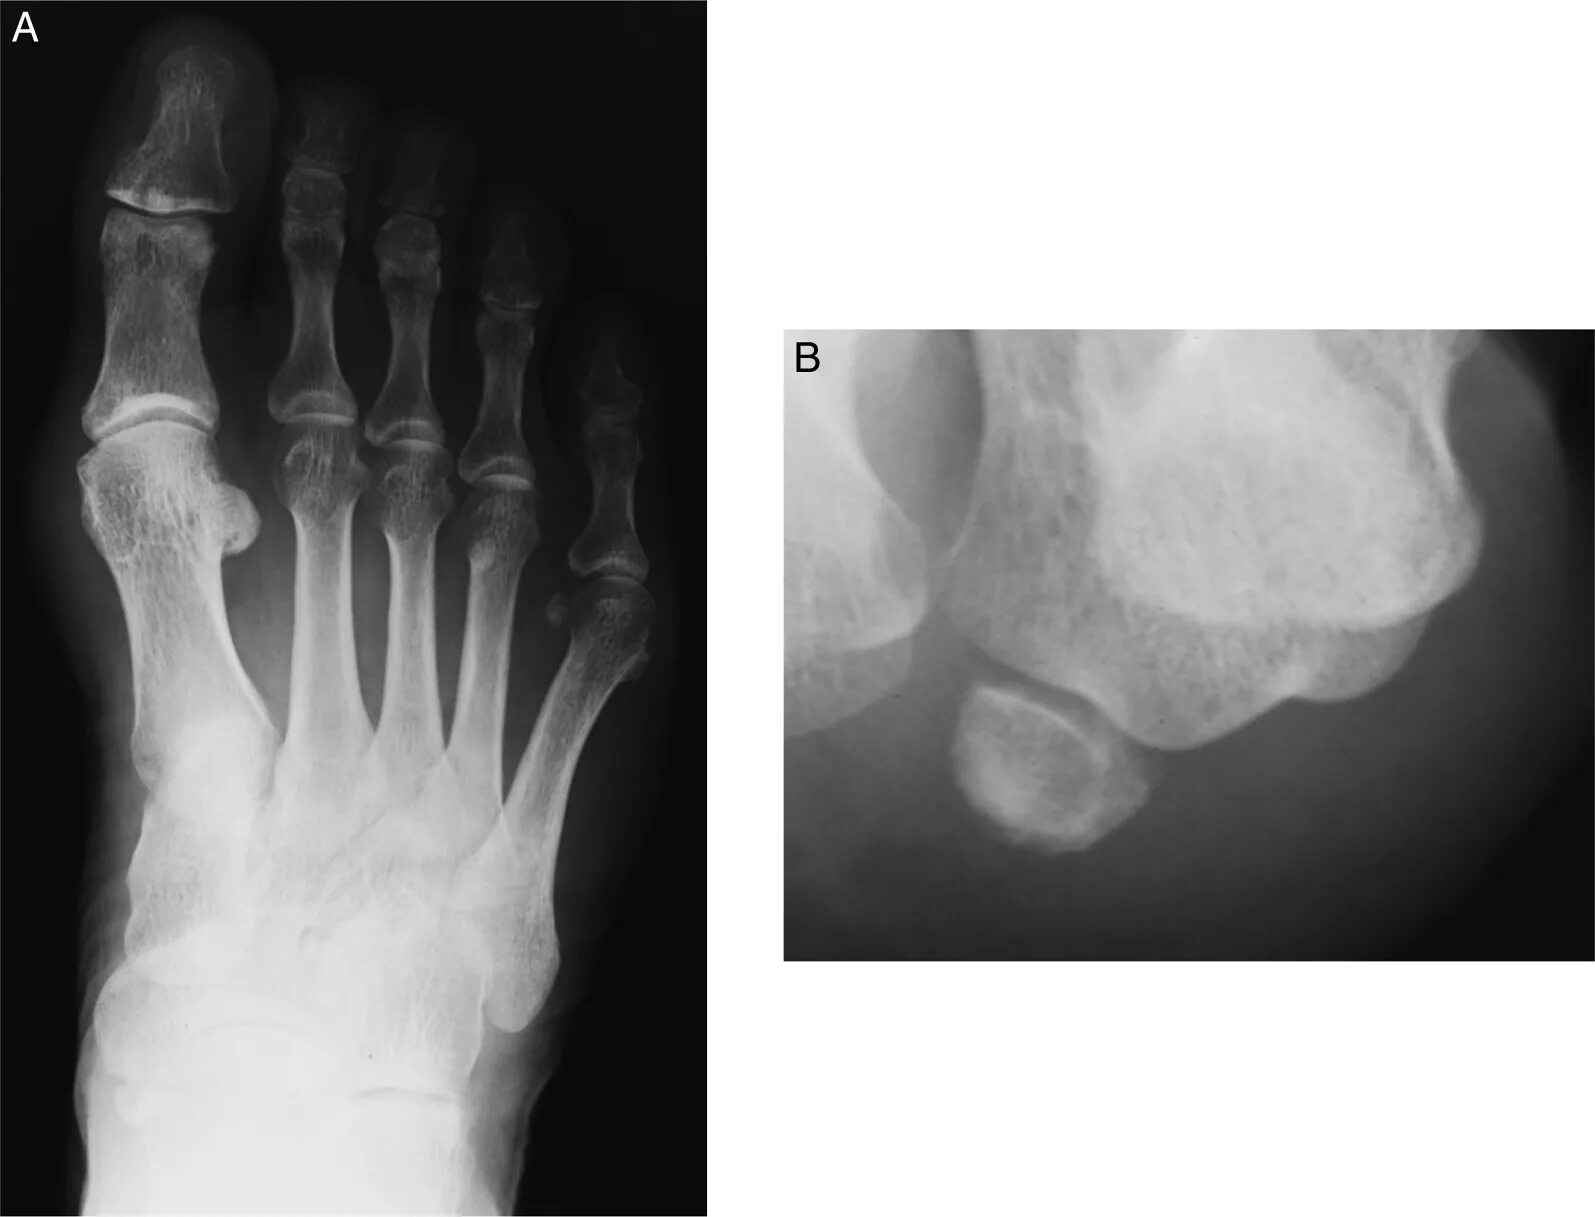

Перелом 3 пястной кости